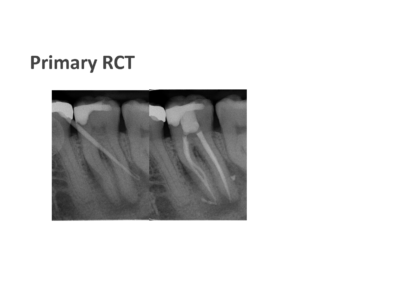

We take pride in providing the highest standard of care at ICE and believe that only the best is good enough for our patients. As such, Shakil completes all endodontic procedures using a state-of-the-art dental microscope. We accept referrals for consultations, root canal treatment (primary and retreatment), management of endodontic emergencies, dentoalveolar trauma and we are also happy to provide definitive restorations as required.